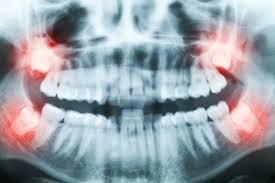

A long time ago, wisdom teeth served a purpose. Today, they can lead to problems if there isn’t enough space to grow or if they come through in the wrong position.

Wisdom teeth are your third set of molars set far back in the mouth. They develop when you’re between the ages of 17 and 25. When the wisdom teeth cause pain and/or are impacted, it’s recommended to get them removed. Let’s look at how these teeth came into being in the first place and what will happen if you need them removed.

Even if the wisdom tooth causes no symptoms, your dentist may recommend removal to prevent further damage or decay. The wisdom tooth will need to be extracted if it is impacted. An impacted wisdom tooth means the tooth is growing in at an odd angle that could affect nearby teeth or that the tooth sits along or within the jawbone.